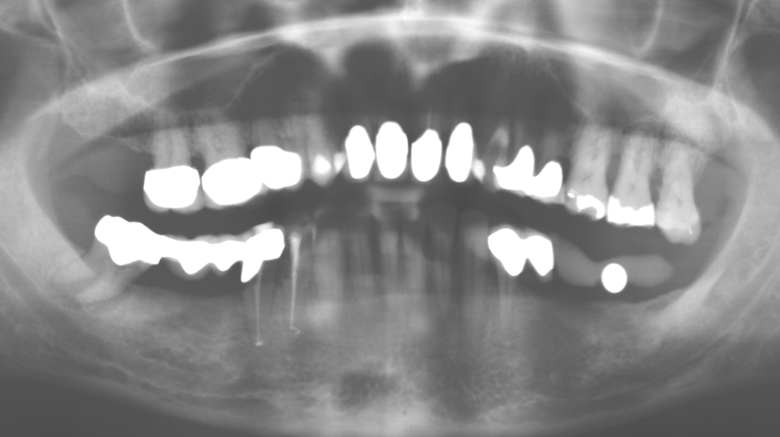

Fig. 1: Panoramic radiograph of initial situation in 2004.

A 52-year-old patient presented in our clinic for the first time in 2004 following tooth loss in the third quadrant, expressing a desire for a new prosthetic restoration. Periodontal and radiological diagnostics revealed the need for extensive periodontological treatment. In addition, teeth 48, 28 and 27 were attributed a very poor prognosis and were subsequently extracted (Fig. 1). Following the successfully completed, systematic periodontological treatment, a fixed dental implant was inserted with the introduction of five implants in tooth regions 35, 36, 37, 46 and 47. Prosthetic treatment of the natural teeth was effected with veneered zirconium dioxide ceramic crowns; the implants were composed of two-piece, individual zirconium dioxide abutments and similarly veneered crowns made of a zirconium dioxide ceramic (Cercon base colored, Dentsply Sirona Lab). Definitive insertion of the prosthetic restoration occurred in 2005.

The ten-year check-up revealed no indications of advancing clinical attachment loss or peri-implant bone substance loss (Fig. 3).

Fig. 3: Panoramic radiograph after ten years with implants.